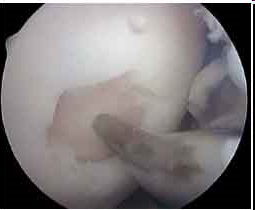

Suture méniscale (fil bleu) stabilisant la déchirure méniscale

Suites opératoires : La revalidation est plus lourde avec une absence d’appui pendant 4-6 semaines, éventuellement un appui partiel 6 semaines, afin de protéger la réparation méniscale.